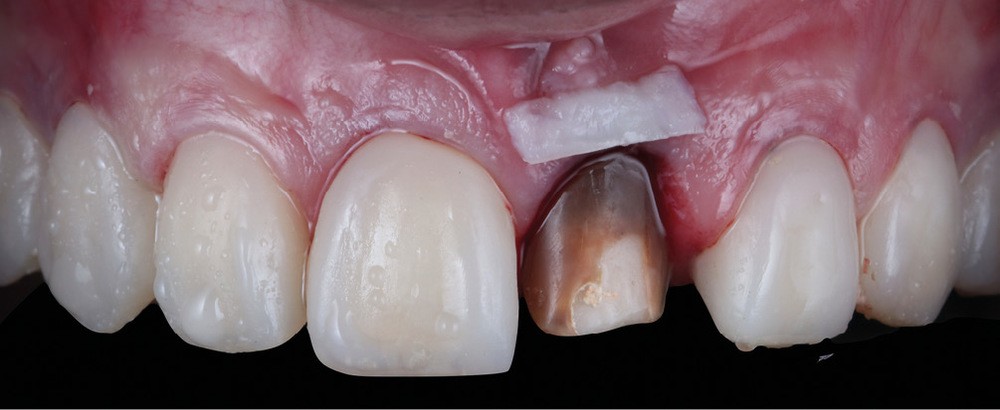

Acte 4 : préparation dentaire et gestion du rose additive (fig. 5 et 6)

À trois mois, les tissus en cours de cicatrisation se stabilisent ; nous passons à la préparation des dents [3].

Au vu des larges plages de cément exposées, nous optons pour une préparation de type couronne sur 53, 11, 21 et 23, afin de privilégier un assemblage prothétique de type scellement. Pour 15, 14, 24 et 25, nous resterons essentiellement dans l’émail et en vestibulaire. Ce choix nous oriente sur une préparation de type facette dont l’assemblage prothétique se fera par collage.

Nous observons que les tissus mous autour de la dent dyschromiée 21 se sont affinés et laissent transparaître le substrat radiculaire [4]. Un épaississement des tissus mous à l’aide d’une greffe de conjonctif s’impose. Dernières retouches également pour la ligne des collets par de petites gingivectomies au bistouri électrique. Des couronnes provisoires, basées sur le nouveau profil d’émergence, sont ensuite posées afin d’obtenir une cicatrisation guidée.